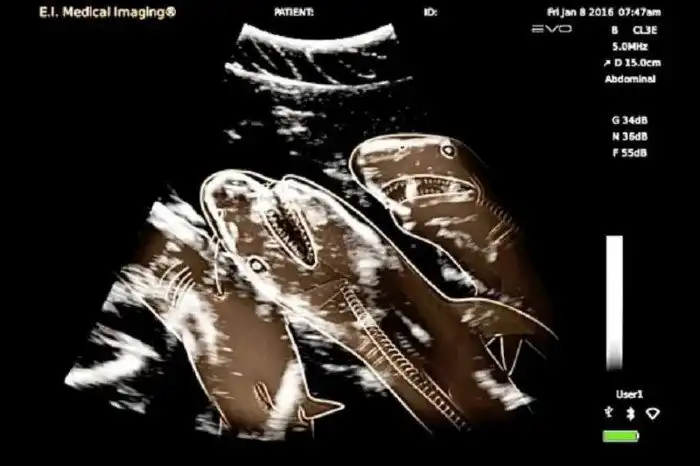

5. УЗИ беременной акулы